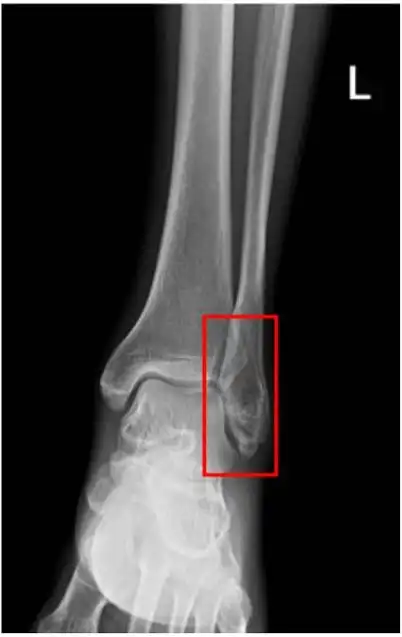

右侧胫腓骨远端似见横行骨折透亮线,断端对位对线尚可然而,一个优秀的